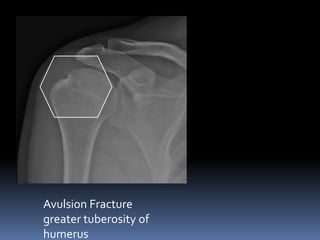

Avulsion Fracture

greater tuberosity of

humerus